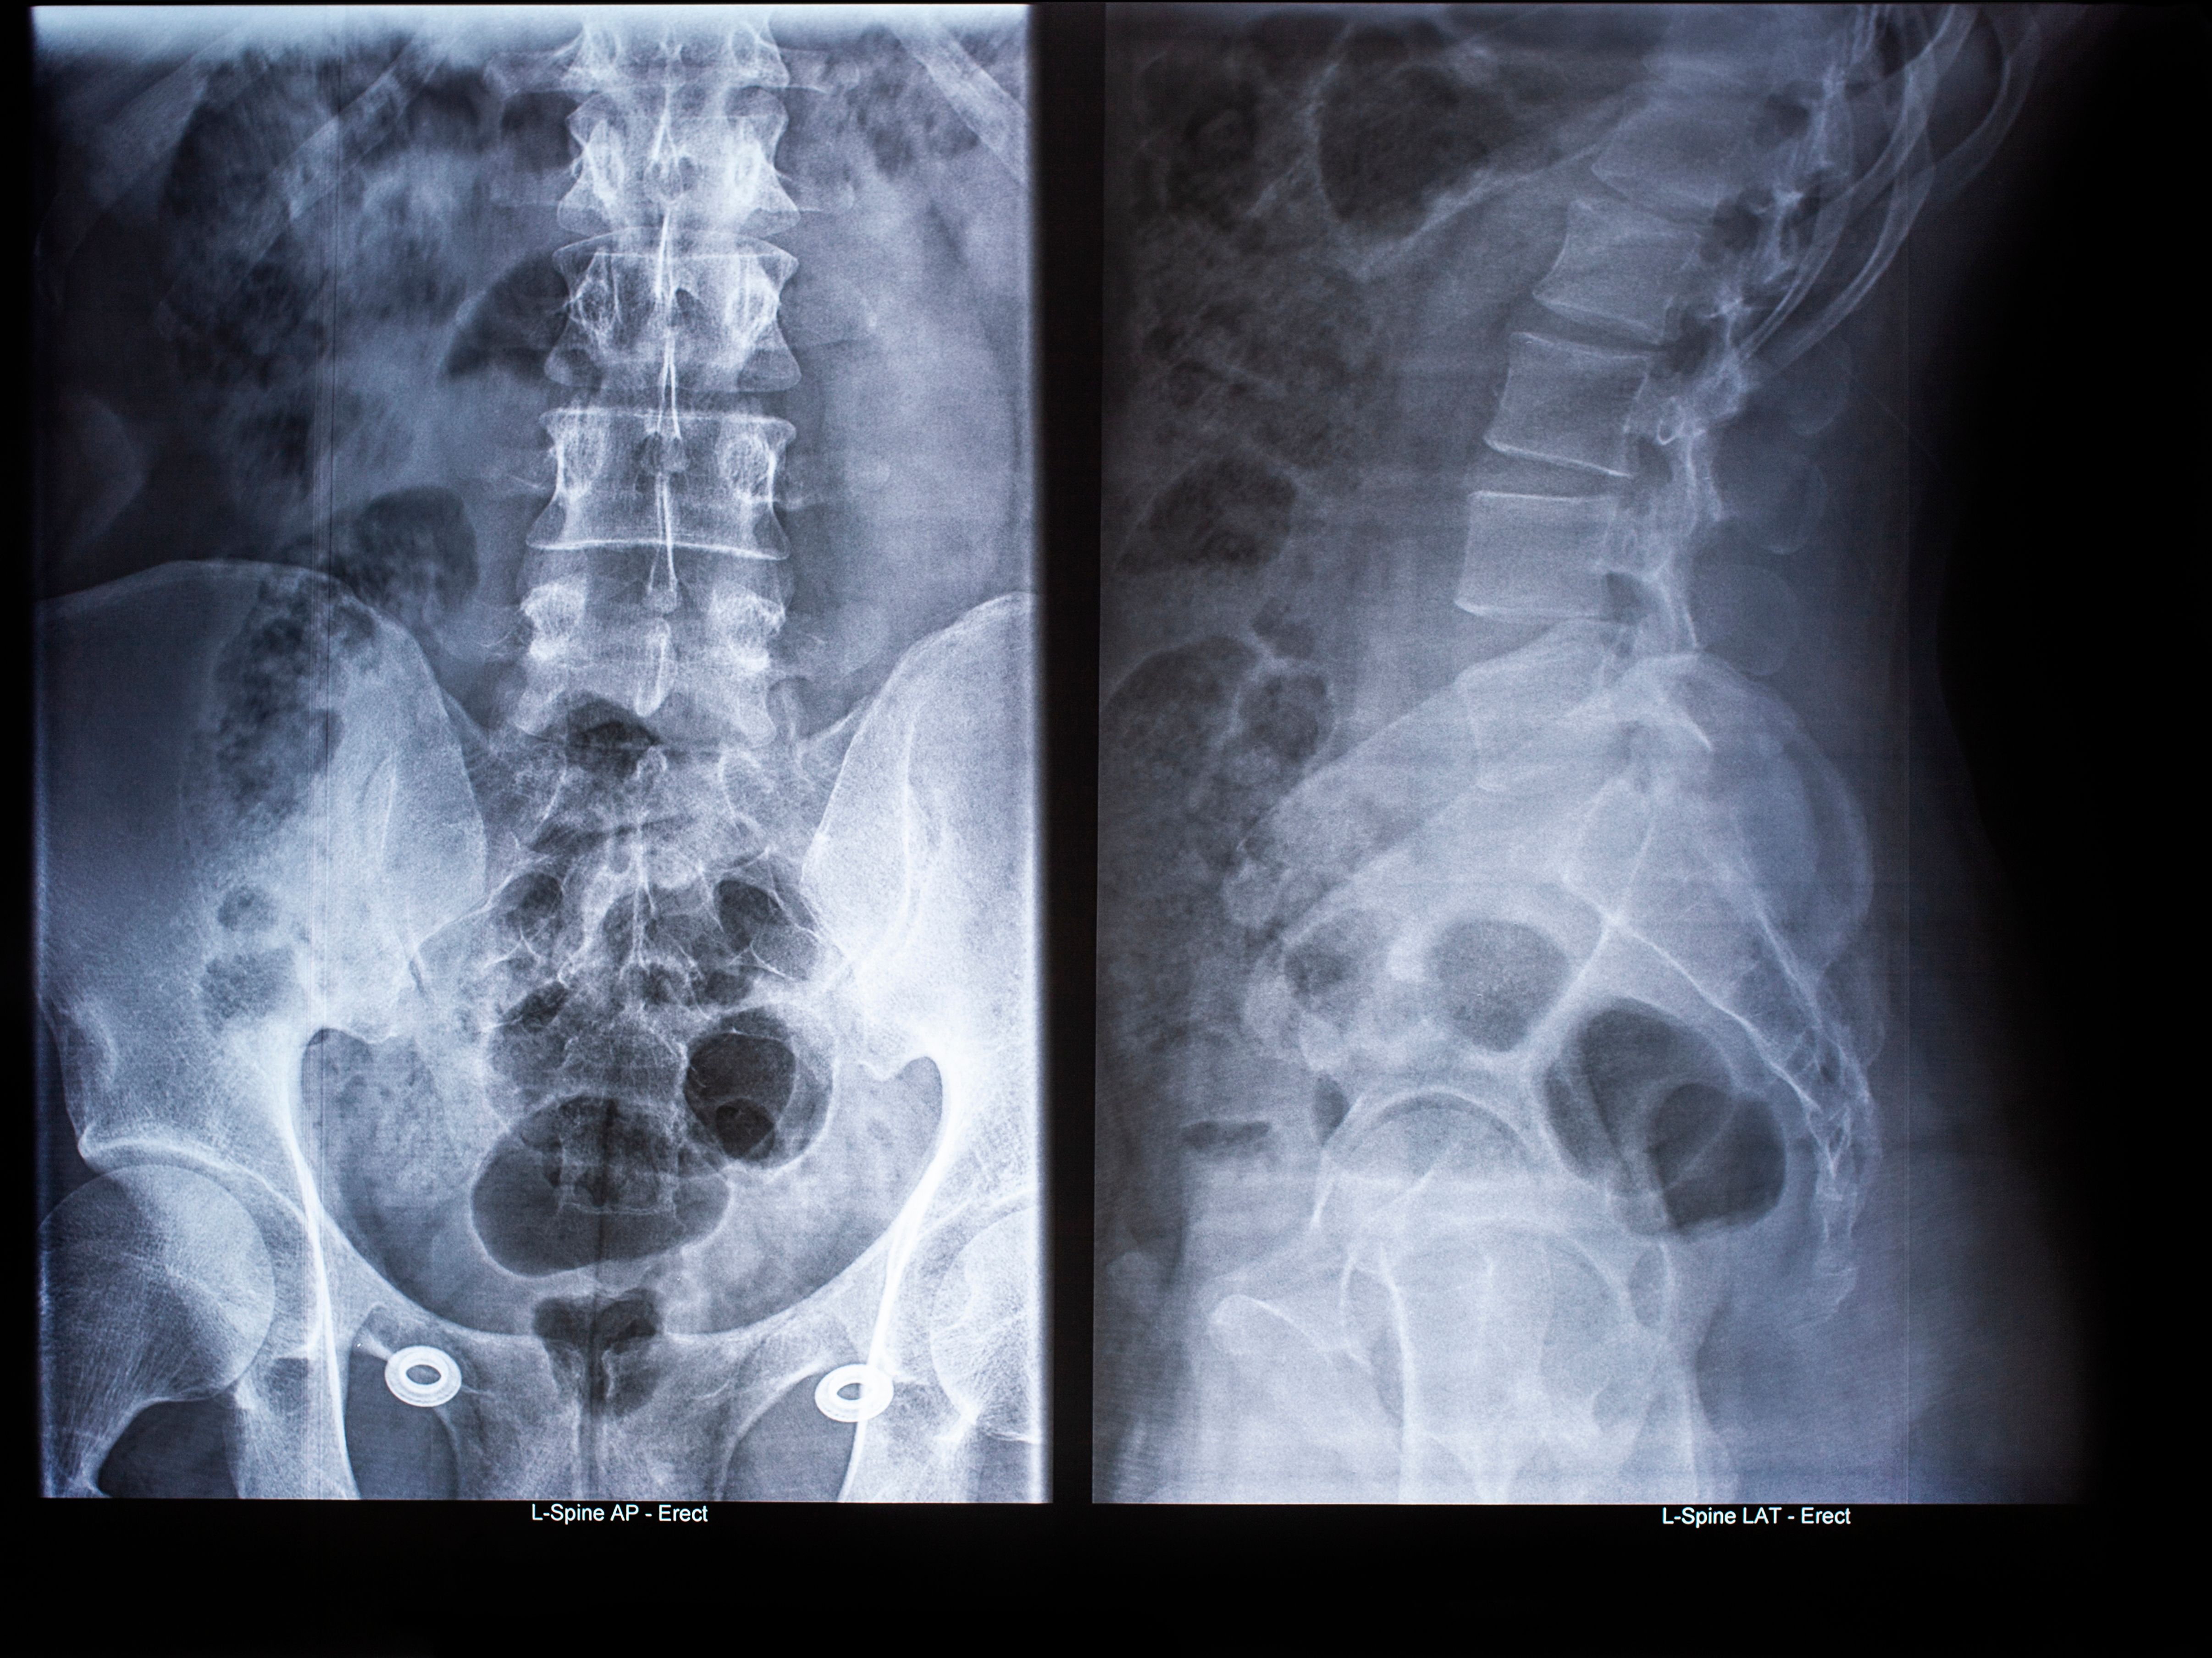

Diagnostic Tests and Imaging

Based on the initial assessment, your doctor may recommend diagnostic tests such as X-rays, MRIs, or CT scans. These imaging techniques provide a detailed view of your spine, helping to pinpoint any abnormalities or areas of concern.

It's natural to have concerns about these tests, but they are crucial for an accurate diagnosis. Your healthcare provider will explain each procedure, ensuring you understand what to expect and how the results will influence your treatment plan.